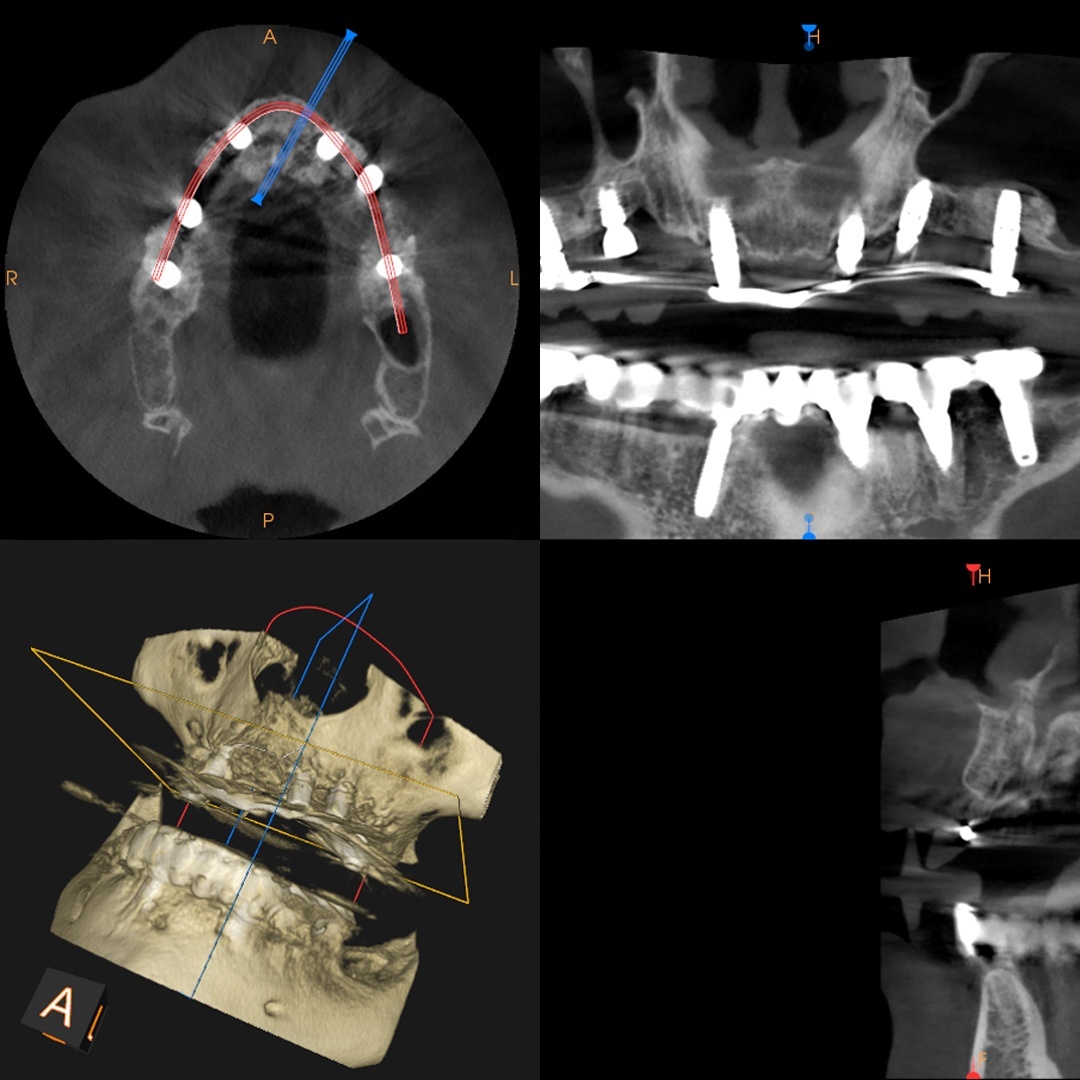

Implant zęba to mała, tytanowa śruba, która jest chirurgicznie osadzana bezpośrednio w kości szczęki lub żuchwy. Zastępuje ona korzeń zęba i stanowi solidną podstawę dla korony, mostu lub protezy.

Wybór odpowiedniego implantu jest kluczowy dla trwałości efektu. W Anna Dental Clinic stawiamy na najwyższą jakość materiałów i nowoczesne technologie, co zapewnia bezpieczeństwo i naturalne odczucia. Dzięki integracji implantu z kością, pacjenci mogą cieszyć się swobodą jedzenia i mówienia bez obaw o przesuwanie się uzupełnień protetycznych.